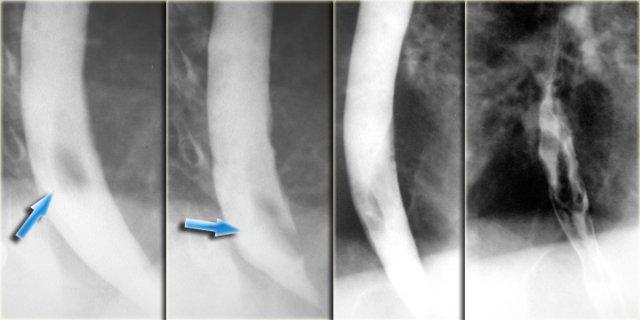

Bên trái là hai trường hợp ung thư dạng polyp.

Ung thư thực quản với các ổ loét (mũi tên) và góc tiếp giáp vuông góc sắc nét với thành thực quản (đầu mũi tên)

Hình ảnh này của một bệnh nhân có ung thư dạng thâm nhiễm loét.

Tổn thương có ranh giới chuyển tiếp đột ngột tạo thành góc nhọn và bờ nhô ra (overhanging edge).

Đặc điểm này gợi ý sự xâm lấn thành thực quản và khác biệt so với góc tù thường gặp trong các tổn thương ngoại sinh không dính vào thực quản.

Các hình ảnh này của một bệnh nhân có ung thư dạng giãn tĩnh mạch.

Hình ảnh các khuyết thuốc không thay đổi gợi ý đây là khối u hơn là giãn tĩnh mạch thực sự.

Lưu ý bờ trên sắc nét của tổn thương và ổ loét (mũi tên)

Ngoài cùng bên trái là hình ảnh của một bệnh nhân có ung thư dạng giãn tĩnh mạch.

Các thùy dài mô phỏng hình ảnh giãn tĩnh mạch nhưng không thay đổi trong quá trình soi huỳnh quang.

Lưu ý các nếp niêm mạc không đều, lớn và khối mô mềm (mũi tên) ở đáy vị

Kế bên là hình ảnh của một bệnh nhân có ung thư lan tràn bề mặt.

Tổn thương lan tràn bề mặt rộng liên quan đến đoạn thực quản xa.

Hình ảnh này có thể gặp ở cả tổn thương sớm lẫn tổn thương tiến triển.